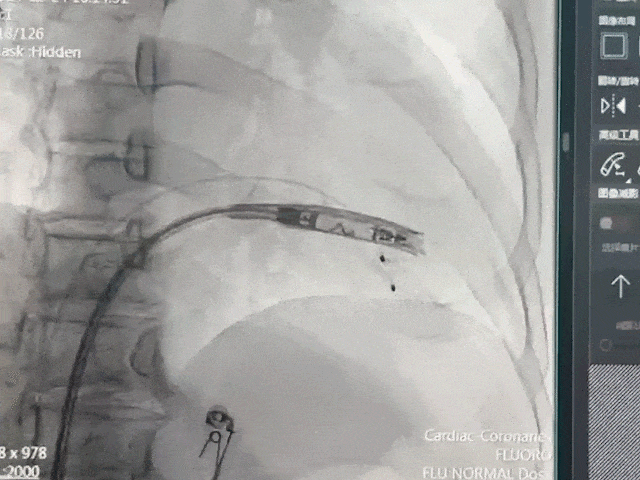

手术过程部分展示

右前30°造影,位置理想

左前45°造影贴靠间隔

后撤保护套筒并释放调弯,保持合适张力,避免前向压力

开始旋入AveirVR